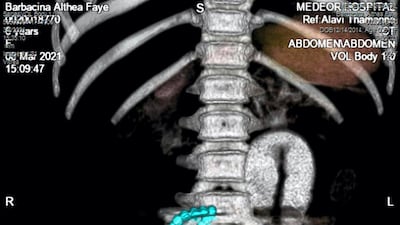

“I was shocked to see some flashy substances in the scan. The intestines were swollen and appeared obstructed, showing high-level infection, which was unusual. I quickly referred the child for a CT scan.

“We found the presence of a metallic substance in the form of a string of beads in the CT scan. But initially, Althea didn’t confirm swallowing anything. Maybe out of fear.

"The foreign substance had already damaged the walls of her intestine in three parts. Ten of the magnetic beads had formed a ring in one place, while one was on the other side of the abdomen.